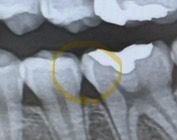

왼쪽 제일끝 어금니 레진으로는 치료가 어려울까요?

원래 레진으로 했다가 가운데가 깨지면서 안쪽으로 충치가 더 생겨서 사진상으로 보이는정도인데 다시 레진은 안될까요?

또 이 사이부분에 충치인것처럼 보이나요..?

• 1번 째 사진

기존치료한걸 다 제거하고 다시 치료를 해야되기 때문에 레진보다는 인레이 치료를 권유합니다. 아래 사진에도 치아 사이에 충치가 잇는것같습니다.

1. 지금 상황으로는 치아에 금이갔을 가능성을 배제할 수 없습니다 레진보다는 크라운이 적합할 수도 있습니다 증상체크해봐랴 할 것 갈습니다

2. 사이 충치 맞을 것 같습니다